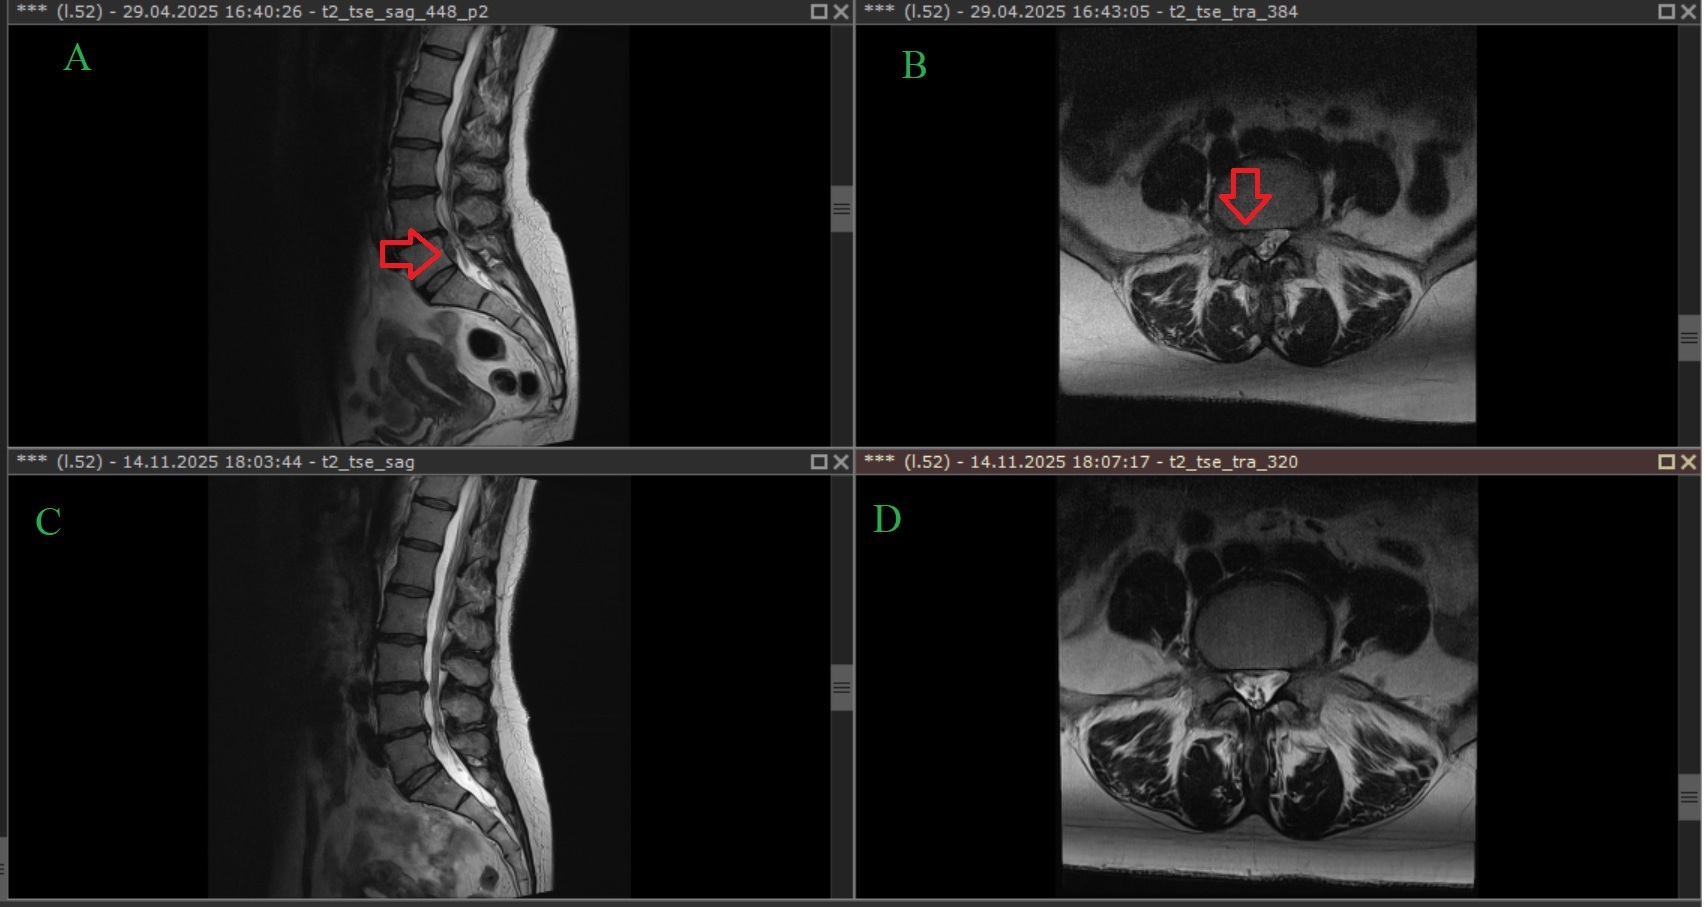

Historia 40-letniej pacjentki, opisana w niedawnych badaniach, jest tego najlepszym przykładem. Przez rok cierpiała na silny ból dolnej części pleców, który promieniował do obu nóg. Jej codzienne funkcjonowanie było znacznie ograniczone, a ból w skali VAS (wizualnej skali analogowej) oceniała na 8 z 10 punktów. Badanie rezonansem magnetycznym (MRI) nie pozostawiało wątpliwości – wykazało dużą przepuklinę dysku na poziomie L5/S1.

Efekty po dwóch latach były zdumiewające. Promieniujący ból w nogach ustąpił całkowicie, a ból pleców zmniejszył się do zaledwie 1 punktu w skali VAS. Co najważniejsze, kontrolne badanie MRI potwierdziło to, co wydawało się niemożliwe: przepuklina dysku uległa spontanicznej resorpcji, czyli została wchłonięta przez organizm. Ten przypadek to potężny dowód na to, jak niezwykłe zdolności regeneracyjne posiada nasze ciało.